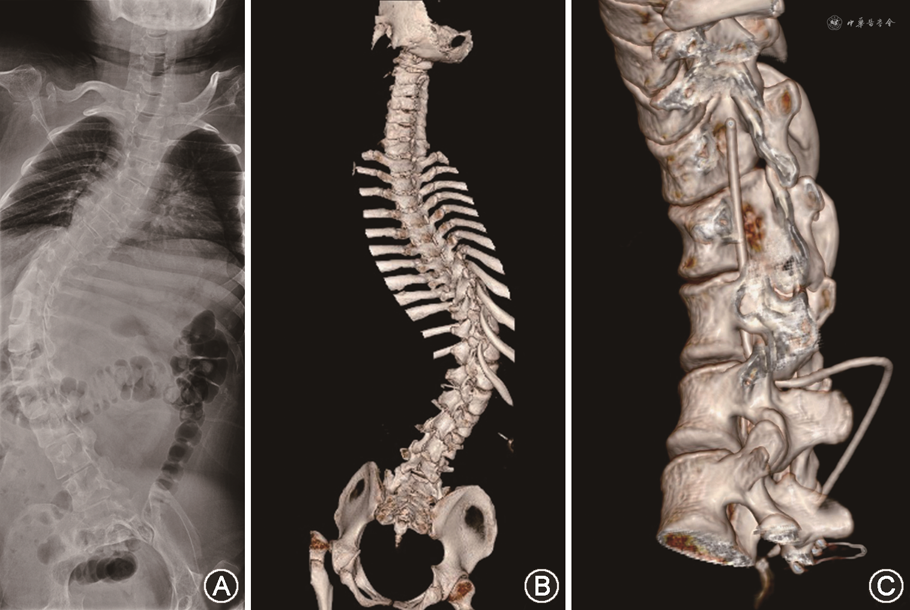

临床资料 患者男性,19岁。2022年1月25日因“进行性四肢无力19年”于山东大学齐鲁医院神经内科就诊。患者于19年前(5个月大时)出现发热,体温最高至39 ℃,随即出现双下肢无力,症状进行性加重,逐渐进展至四肢无力;18年前(1岁时)于当地医院就诊,考虑为脑瘫,未行特殊治疗,患者尚能自行翻身,扶栏杆可站立,无吞咽困难及饮水呛咳,无呼吸困难;16年前(3岁时)于北京儿童医院就诊,考虑为SMA,未行特殊治疗;9年前(10岁时)于北京协和医院就诊,基因检测示运动神经元存活基因(survival motor neuron gene,SMN)1(SMN1)外显子7纯合性缺失;8年前(11岁时)于山东大学附属生殖医院行分子遗传检测示SMN1基因7、8外显子大片段纯合缺失突变,SMN2基因拷贝数为3,结合临床考虑为SMA2型。患者2022年1月就诊于我院神经内科,完善评估及相关检查后,拟行腰椎穿刺术鞘内注射诺西那生。入院体格检查:意识清楚,精神差,双肘关节、左手尺侧三指屈曲畸形,脊柱侧弯畸形,双侧跟腱挛缩,双肩关节内收、外展肌力0级,双肘屈肌力Ⅱ级、伸肌力0级,双侧腕屈肌力Ⅲ级、伸肌力Ⅱ级,双手拇、食指屈、伸肌力Ⅳ级,余3指屈肌力Ⅲ级、伸肌力0级,双侧髋关节和膝关节屈、伸肌力Ⅰ级,双足趾屈、伸肌力Ⅲ级。双侧指鼻试验、跟膝胫试验无法完成,双侧病理征阴性。术前行全脊柱X线及CT三维重建,明确患者脊柱侧弯畸形情况(图1A、B)。因患者严重脊柱侧弯畸形,腰椎穿刺难度大,腰椎穿刺鞘内注射由我院麻醉科医师操作。麻醉科完成2次穿刺鞘内注射后,第3次腰椎穿刺失败,超声引导下定位穿刺亦未成功。经院内多学科会诊讨论,认为腰椎穿刺难度大,患者需要按时、长期给药,多次反复穿刺引起穿刺部位疼痛,患者有治疗抵触情绪,腰椎穿刺失败后影响患者治疗效果。神经外科提出,可以借鉴Ommaya囊脑室植入术的理念,进行腰段蛛网膜下腔Ommaya囊系统植入,将导管置于脊髓蛛网膜下腔,储液囊置于皮下,通过穿刺储液囊,将诺西那生注射至蛛网膜下腔,以达到治疗目的。该方案在多学科讨论会上获得统一意见后,择期进行腰段蛛网膜下腔Ommaya囊系统植入术。

手术过程:术前行脊柱CT三维重建,确定L1~2为植入间隙,棘间注射美兰定位。全身麻醉成功后,取左侧卧位,标记后正中以定位点为中心长约4 cm直切口以及右侧腋后线长约3 cm直切口(图2A)。切开后于正中切口皮肤及皮下各层,分离椎旁肌,暴露侧弯的棘突。根据术前美兰定位及上下棘突的位置,确定L1、2的椎板。磨除L1的部分下椎板及L2的部分上椎板,显露大小约5 mm× 5 mm硬脊膜囊(图2B)。显微镜下弧形打开约2 mm硬脊膜及蛛网膜,将分流管置入腰大池蛛网膜下腔约10 cm,见脑脊液流出通畅(图2C),严密缝合硬脊膜并固定导管。切开腋后线切口至皮下筋膜层,建立两切口间皮下隧道,将分流管的储液囊端通过皮下隧道到达腋后线切口,与储液囊相连接并固定(图2D、E)。将储液囊用丝线固定于筋膜层,用5.5号穿刺针穿刺储液囊并抽吸,见脑脊液流出通畅(图2F)。依次缝合两处切口,无菌敷料包扎,患者麻醉清醒后拔除气管插管安全返回病房。术后患者体温正常,无感染,刀口愈合良好,行脊柱CT三维重建,见Ommaya储液囊及导管位置良好(图1C)。术后7 d患者经皮穿刺Ommaya储液囊给药,穿刺成功后回抽,针管中可见无色清亮脑脊液,抽取脑脊液5 ml后,将诺西那生缓慢推注入蛛网膜下腔,2 ml生理盐水冲管,术后无菌敷料包扎(图2G)。患者给药后第2天拆线出院,出院时一般情况良好,与入院时无明显变化。Ommaya囊植入后,患者共穿刺给药3次,体格检查肌力无明显变化,未出现穿刺部位出血或蛛网膜下腔感染等并发症。